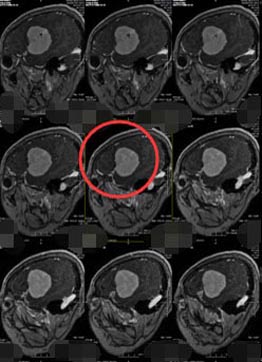

半年前,曾阿姨的手抖动频率增加,家人觉得还是去医院做个检查放心一些。头颅CT示“右侧颞叶占位性病变,考虑脑膜瘤可能”,当地医院的医生告诉他,肿瘤大小已经是40mm×33mm×49mm,建议转上级医疗机构进一步检查和治疗。

入科时查体:反应迟钝,言语缓慢,记忆力、理解力明显变差,右侧肢体肌力V级-,右侧肢体不自主抖动。头颅MR检查结果示:右侧额颞部颅骨内板下占位性病变,考虑脑膜瘤可能性大。头颅CTA检查结果示:右侧额颞部占位性病变血管较丰富,病变推压右侧大脑中动脉远端分支侧呈抱球状改变。